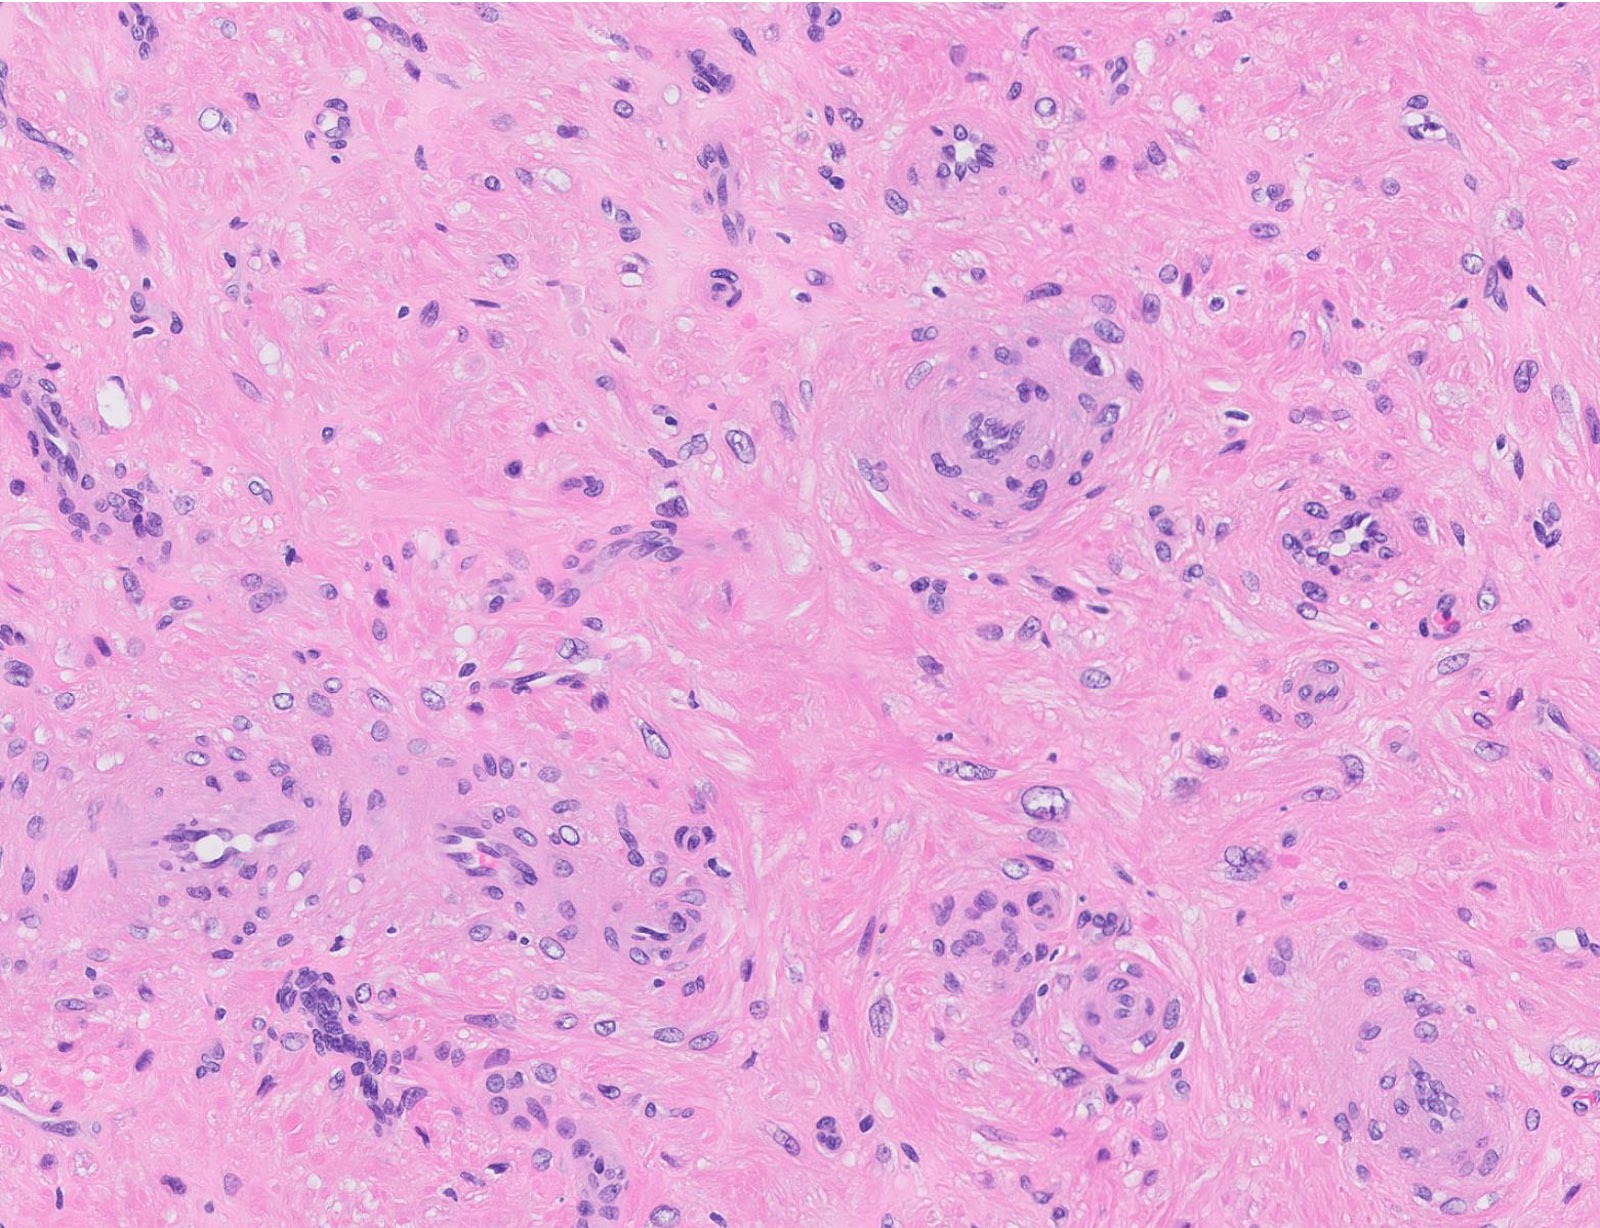

Microscopic (histologic) description

- Encapsulated proliferation of eosinophilic smooth muscle cells with minimal nuclear pleomorphism

- Rounded or slit-like veins with muscular walls present within the tumor (J Cutan Pathol 2017;44:342)

- Tumors can further be classified into 3 subcategories, first described by Morimoto et al:

- Solid type: smooth muscle bundles surround numerous small slit-like channels

- Cavernous type: dilated vascular channels, the walls of which are difficult to distinguish from the intervascular smooth muscle

- Venous type: thick walled vessels that are easily distinguished from the intervascular smooth muscle

- Epithelioid and pleomorphic variants are reported in a few cases

- Epithelioid type: composed of cells with round to oval nuclei and a moderate amount of finely granular eosinophilic cytoplasm with occasional vacuoles (Am J Dermatopathol 1998;20:213)

- Pleomorphic type: marked nuclear pleomorphism but only rare or absent mitoses (Am J Dermatopathol 2000;22:268)

- Calcification and marked degeneration, including hyalinization and myxoid changes, may be present (J Cutan Pathol 2017;44:342, J Ultrasound Med 2019;38:1201)

- Fat can be seen in a few cases; not to be mistaken for angiomyolipoma (Cancer 1984;54:126)

Microscopic (histologic) images

Contributed by Ohoud Aljarbou, M.D., Jijgee Munkhdelger, M.D., Ph.D. and Andrey Bychkov, M.D., Ph.D.

A. Angioleiomyoma. A mixture of smooth muscle bundles arranged in small fascicles and intervening vascular channels is noted. The concentric perivascular spindle cell proliferation which is characteristic for myopericytoma is absent. There are no glomus cells seen. Adipocytes are not seen in this image, which makes angiomyolipoma less likely.